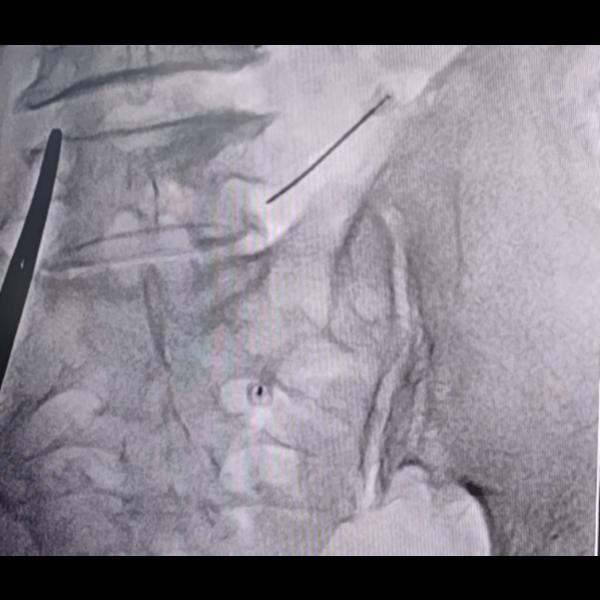

Transforaminal L4,L5,S1 nerve root block !

View Details